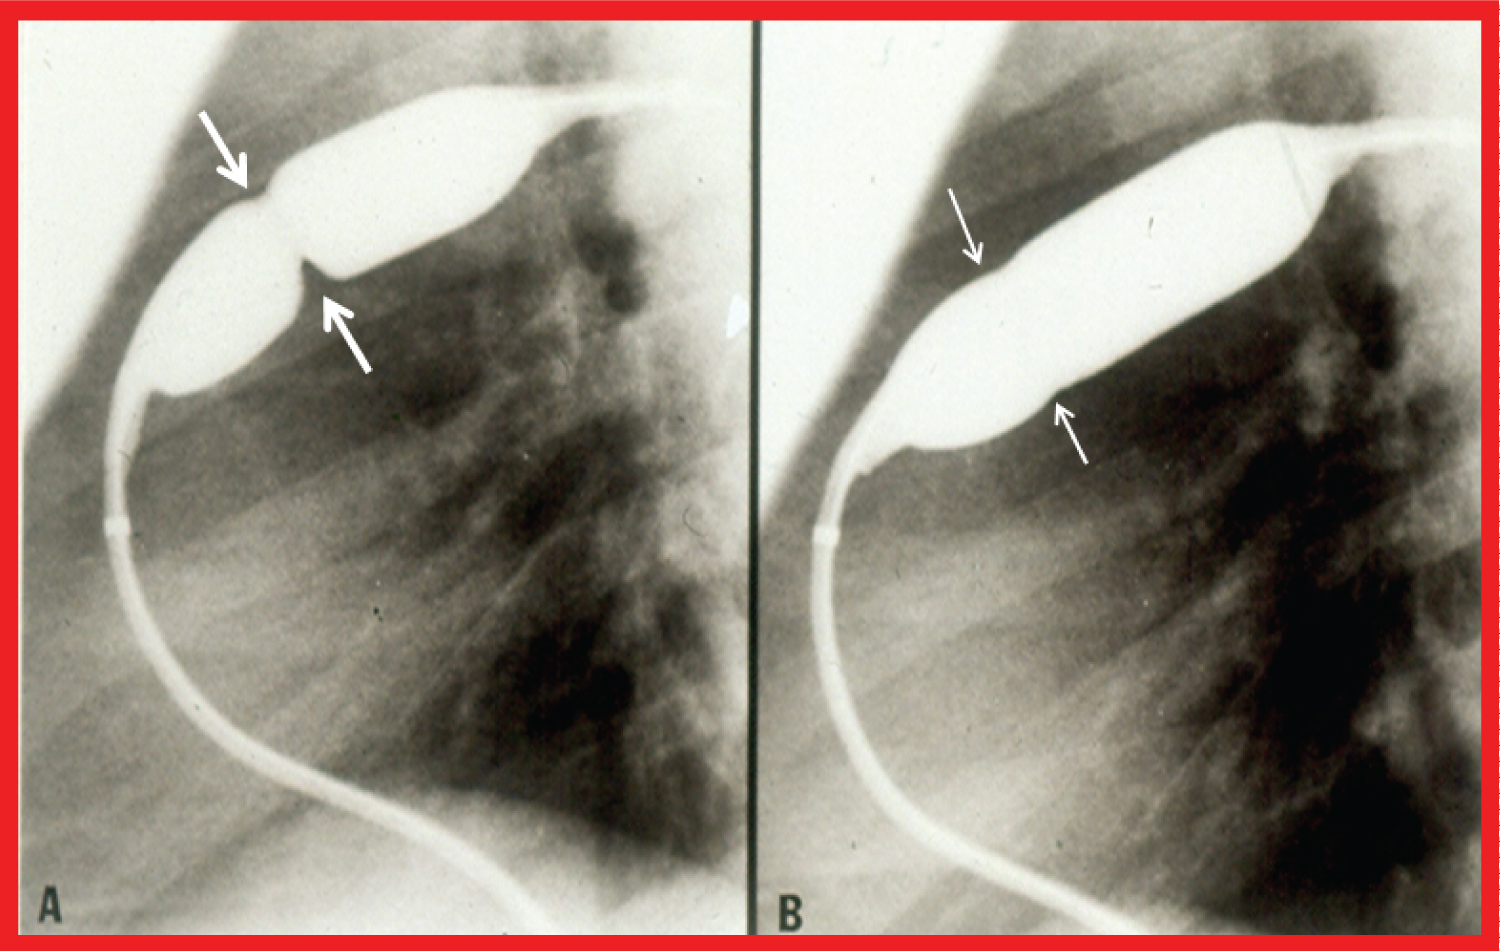

Historical aspects, indications, procedure of BPV, and immediate and follow-up results in patients with pulmonary stenosis associated with cyanotic CHDs were appraised [46-52]. BPV is recommended if the infant/child needs palliation of pulmonary oligemia but is not a candidate for total surgical correction at presentation. The procedure is indicated if the pulmonary valve obstruction is a significant part of the right ventricular outflow tract stenosis and multiple obstructions in series exist (Figure 4) so that there is likely to be residual subvalvar obstruction following relief of valvar narrowing so that flooding of the lungs is prevented. Increase in systemic arterial saturations immediately after BPV and growth of the pulmonary arteries at follow-up (Figure 5) seem to be the benefits of BPV in this subset of patients.

Figure 4: Selected cineangiographic frames from patients with tetralogy of Fallot (left) and d-transposition of the great arteries (right), demonstrating two sites of pulmonary outflow obstruction (two arrows). When the pulmonary valve obstruction is relieved by balloon valvuloplasty, the subvalvar obstruction remains and prevents the flooding of the lungs [48].

Ao: Aorta; LV: Left Ventricle; PA: Pulmonary Artery; RV: Right Ventricle View Figure 4

Figure 5: A) Selected frames from pulmonary artery cineangiograms in a sitting-up view in a patient with tetralogy of Fallot, prior to and B) 12 months following balloon pulmonary valvuloplasty. Note the significant improvement in the size of the valve annulus and main pulmonary artery (MPA) at follow-up [48].

LPA: Left Pulmonary Artery; RPA: Right Pulmonary Artery View Figure 5